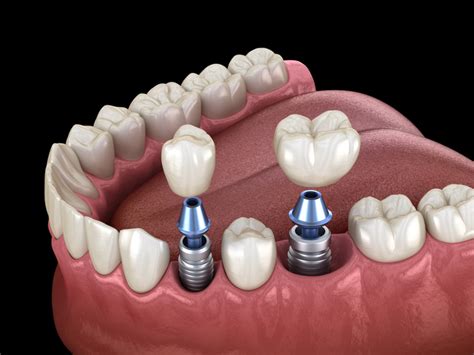

Los implantes dentales sin tornillos o también conocidos como implantes subperiósticos son un tipo de tratamiento que se utilizan en personas con poco hueso mandibular o maxilar. A diferencia de los implantes tradicionales, los subperiósticos no se insertan directamente en el tejido óseo, sino que se colocan bajo la encía y alrededor del hueso maxilar o mandibular con unas pequeñas inserciones laterales que permiten mayor fijación y estabilidad.

- Colocación de la estructura de titanio: Durante la cirugía el especialista hace un corte en la encía y abre un colgajo, después coloca la estructura de titanio sobre el hueso, ajustándose perfectamente a la forma del tejido óseo y fijándolo lateralmente con pequeños aditamentos que le dan mayor sujeción y estabilidad.

- Colocación de la prótesis: Toda rehabilitación con implantes sin tornillos consta de dos fases, en la primera se coloca una prótesis provisional, la cual viene prefabricada y permite al paciente tener dientes apenas termina la intervención. Una vez superada la etapa de integración se procede a la toma de medidas para la fabricación de una prótesis definitiva, puede ser de metal porcelana, metal acrílico o de zirconio.